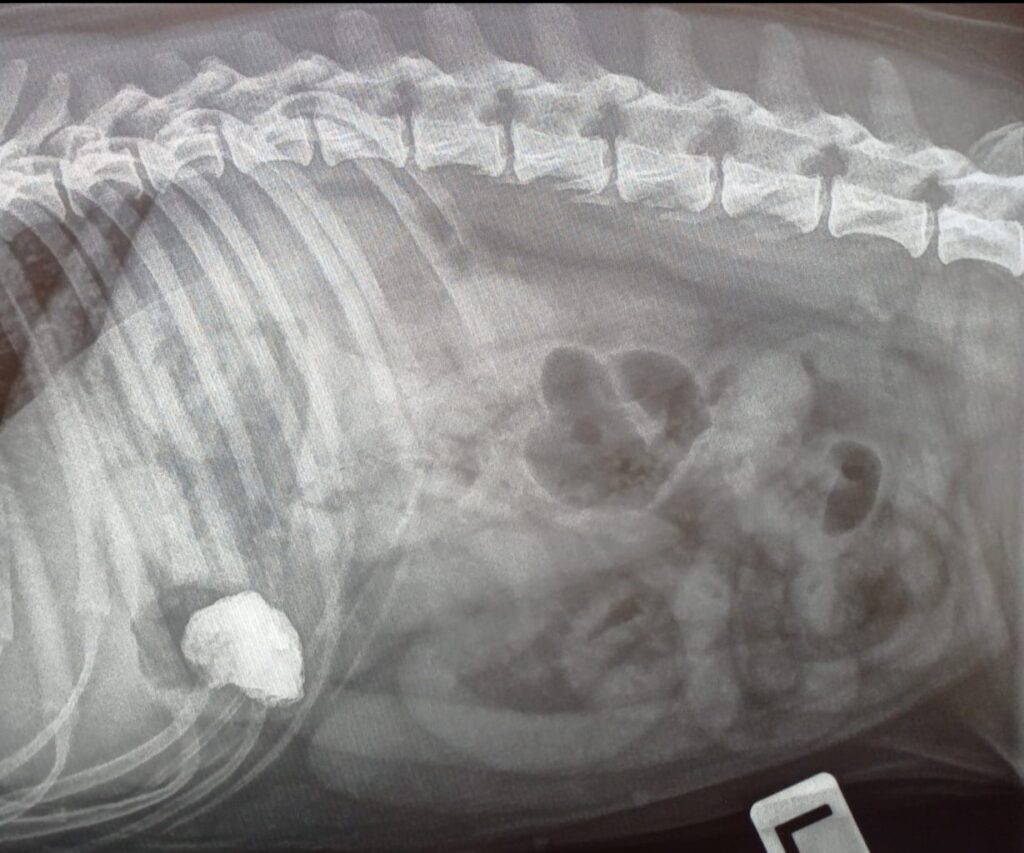

Ester päätettiin rauhoittaa kevyesti röntgenkuvantamista varten. Rauhoituksessa Esteriltä otettiin 3 röntgenkuvaa vatsaontelosta useasta eri suunnasta, näissä näkyy mineraalitiheä ja teräväreunainen vierasesine vatsalaukun alueella (susp. kivi). Koska kivi oli suhteellisen suuri Esterin kokoon nähden, päädyttiin, että kiven leikkauksellinen poisto on suositeltavaa. Kivi ei sula ruoansulatuskanavassa ja voi aiheuttaa suolistossa suolitukoksen. Teräväreuneinen kivi voi myös vahingoittaa suolen seinämää ja pahimmillaan puhkaista sen. Suuren, teräväreunaisen vierasesineen oksennuttaminen ei myöskään ole turvallista, koska vierasesine voi jäädä jumiin ruokatorveen tai vahingoittaa ruokatorvea.